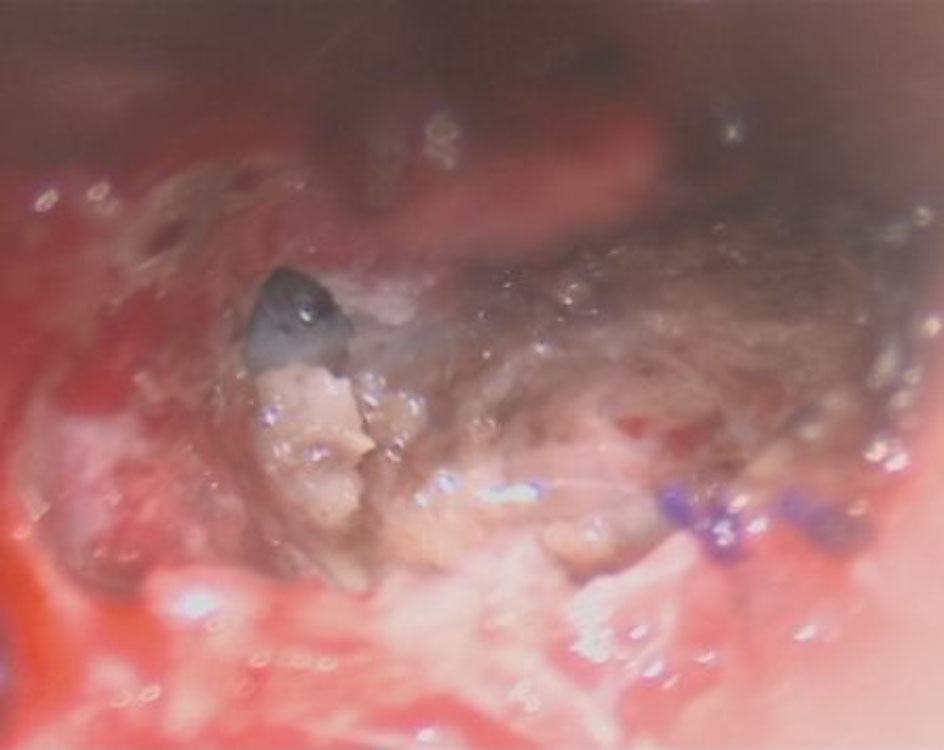

618

'25年4月

40代

小脳血管芽腫

頭蓋内腫瘍摘出術

No.’25_20 摘出 前

No.’25_20  摘出 中

No.’25_20 摘出 後